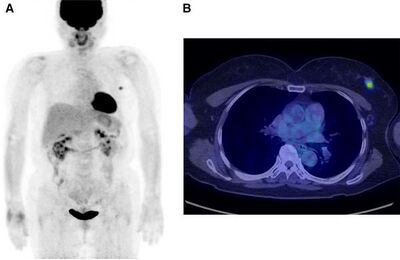

Fludeoxyglucose (18F) is a glucose analog with the positron-emitting radionuclide fluorine-18 substituted for the normal hydroxyl group at the C2 position in the glucose molecule (FDG) [5]. This is the most common radiotracer for PET imaging, especially in clinical oncology. PET imaging is significant in clinical oncology because it can show all the detectable disease in the body with high accuracy. Anaerobic glycolysis is an early indicator of malignant transformation of cells. Using PET imaging with FDG enables analysis of the glucose metabolism throughout the entire body in a single examination. Similarly, PET imaging can be used to assess the therapeutic response of cancer treatments [5]. Uptake of FDG by the tumor can usually be detected with a PET scanner about 45 to 90 minutes after injection [7]. FDG-PET imaging is helpful for primary tumor detection and diagnosis, assessing metastases, and monitoring response to therapy (Figure 6). In pre-operative testing, high uptake of FDG by tumors is observed, especially in ductal carcinomas, but FDG itself is not tumor specific and cannot detect malignant from benign cells. For this reason, false positives can occur when activated inflammatory cells exist [7].

HER2, which is overexpressed in 25 to 30 percent of breast cancer patients, is involved in tumor cell survival, proliferation, maturation, metastasis, and angiogenesis. Trastuzumab, an antibody against HER2, is widely used in targeting HER2. HER2 expression is determined using immunohistochemistry (selectively imaging antigens by exploiting antibodies binding specifically to antigens in tissue), or fluorescence. However, these techniques cannot be used when the tumor cannot be easily accessed for a biopsy. Additionally, HER2 expression can vary during the course of the disease. In order to avoid these complications, PET imaging can be used to non-invasively determine HER2 expression. Currently, HER2 antibodies have been labeled with 124I, 86Y, 76Br, 89Zr, and 64Cu for PET imaging. Use of 64Cu-trastuzumab allowed for primary tumor lesions larger than 2 centimeters in diameter, and metastatic brain lesions larger than 1 centimeter in diameter to be visualized (Figure 7).